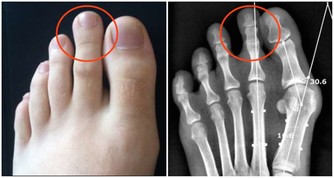

2. 你會出現肌肉痙攣

鉀對肌肉的有效運作至關重要,所以當鉀水平低時,你可能會覺得疼痛,甚至痙攣痛。